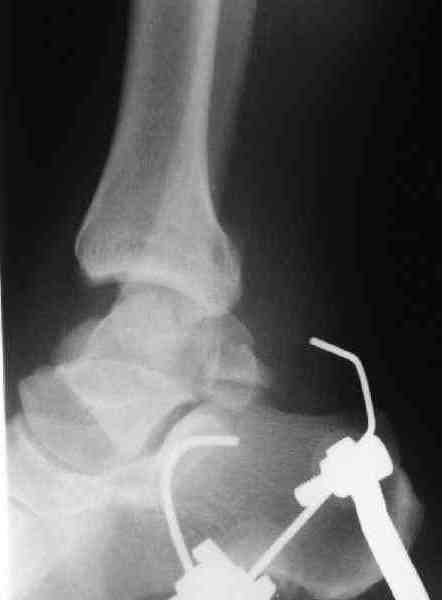

Re: повреждение таранной кости

послал Maxim Agalakov 18 Июнь 2007, 22:59

Для оценки состояния нужны дополнительные исследования, например

> Canale или Broden ренгенограммы

повторили рентгенограммы и доделали проекции, к единому мнению все еще не пришли